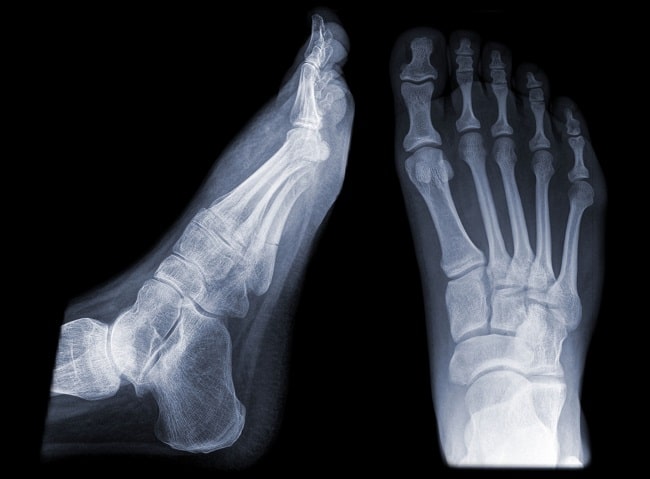

Rontgen ankle dan kaki atau “ankle and foot X-ray” merupakan pemeriksaan radiologi yang memanfaatkan sinar-X untuk mengevaluasi tulang dan jaringan lunak di sekitar pergelangan kaki dan kaki. Rontgen ini umumnya dilakukan sebagai pemeriksaan inisial pada trauma akut muskuloskeletal, infeksi, arthropati kronis, dan tumor pada tulang atau jaringan lunak kaki.[1]

Keunggulan rontgen dibandingkan modalitas radiologi lainnya adalah ketersediaannya yang luas dan biayanya yang relatif lebih murah. Rontgen ankle dapat diindikasikan untuk konfirmasi fraktur pergelangan kaki, sedangkan rontgen kaki dapat diindikasikan untuk konfirmasi fraktur metatarsal atau tulang kaki lainnya. Untuk menentukan apakah pasien yang mengalami trauma ankle atau kaki memerlukan rontgen, Ottawa Ankle and Foot Rule dapat dijadikan acuan.[1,2]

Hasil rontgen ankle dan kaki juga dapat menunjukkan tanda-tanda seperti efusi sendi maupun pembengkakan jaringan lunak yang berguna untuk identifikasi cedera yang tersembunyi (occult injuries). Kalsifikasi jaringan lunak pada hasil rontgen juga dapat menjadi tanda penyakit jaringan lunak, arthropati, hingga tumor.[2]